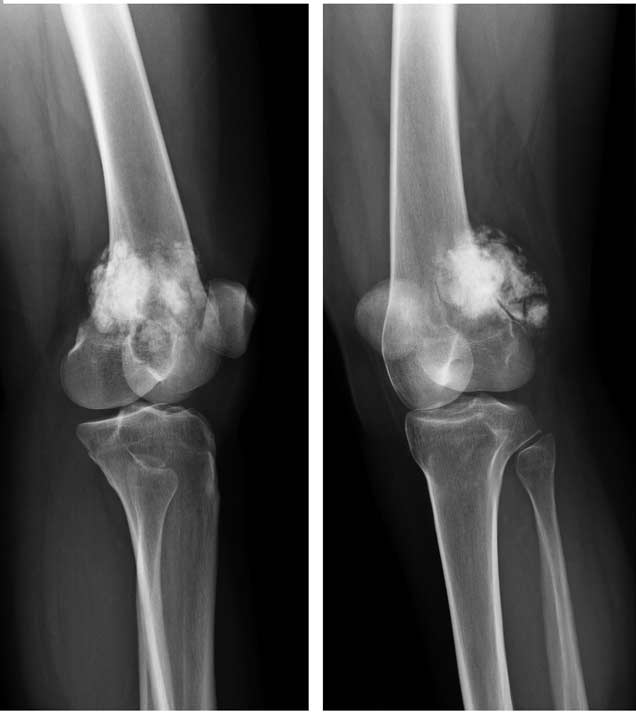

Диагноз ставят с помощью рентгенологического метода и КТ, а подтверждают гистологически. Лечение – комбинированное: оперативное удаление и химиотерапия.

Развитие патологии

Замечено, что остеосаркома чаще всего развивается в тканях длинных трубчатых костей, к которым относится и бедренная кость. На ее долю выпадает основное количество диагностированных случаев описываемого заболевания – приблизительно в 80% всех диагностированных случаев остеогенных сарком был поражен дистальный конец бедренной кости (тот, который принимает участие в формировании коленного сустава). Такая статистическая закономерность касается всех возрастных групп, у представителей которых было выявлено описываемое заболевание.

- рентгенологическое исследование – его информативность не всегда удовлетворяет, но метод позволяет выявить опухоль в месте развития остеосаркомы, а при ее прогрессировании – существенный дефект тканей. К тому же, рентгенологические аппараты имеются даже в небольших клиниках – с их помощью ставят предварительный диагноз, после чего есть смысл направить пациента на прохождение более информативных методов исследования;

- компьютерная томография (КТ) – компьютерные срезы позволяют детально изучить структуру костной ткани в месте поражения;